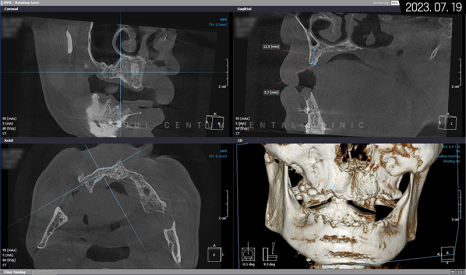

파노라마 엑스레이 사진을 보면 뿌리 주변이 골 소실로 인해 까맣다는 것을 확인할 수 있습니다.

그래서 아래턱을 보존할 수 없는 영구치를 먼저 발치하고 임시 틀니를 사용하면서 저작 기능을 갖기로 했죠. 상악은 픽스처를 고정했고 위턱뼈 어금니 위의 상악동막이 내려왔기 때문에 측방 상악동 거상술도 시행해야 했습니다. 나머지 치조체는 픽스처 고정 위치에 따라 치조정 술식으로 뼈이식재를 넣기로 했습니다.

위턱뼈의 1차 인공 치근 식립을 마치고 나서 3~4개월 후 2차 힐링 어버트먼트를 연결하기로 했으며 동시에 아래턱도 자가골 유도 재생이 어느 정도 진행되었기에 필요시 치조골 이식과 함께 픽스처를 고정해서 1차 수술을 마무리하기로 했습니다.